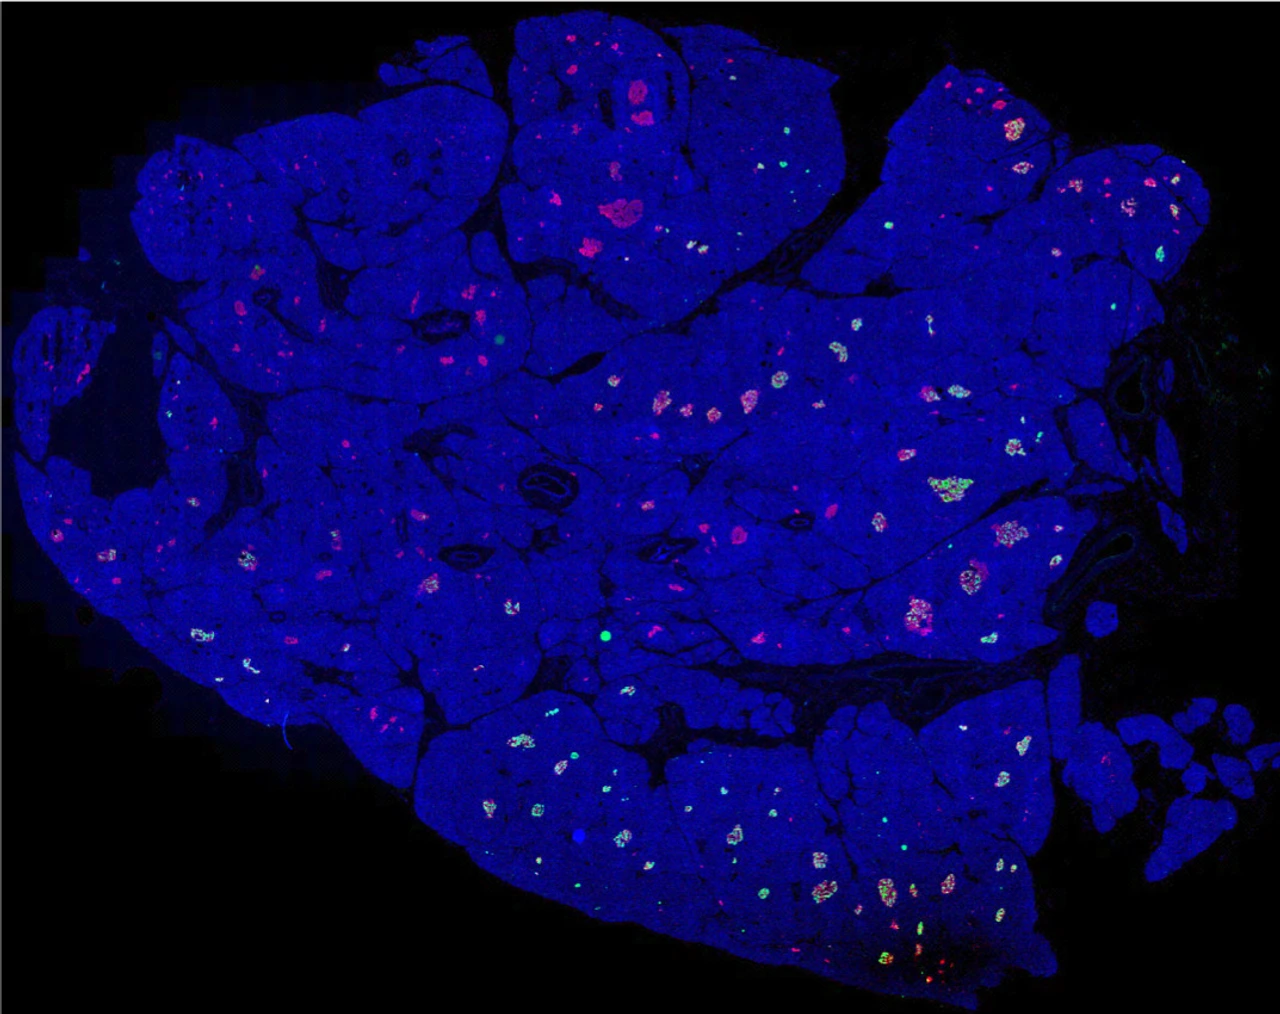

Rodriguez-Calvo_pancreas_whole

Whole slide imaging of the pancreas to study type 1 diabetes

Collaboration with Zeiss